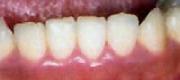

【ケース1】 メラニン(歯ぐきの黒ずみ)の除去例

【治療前】

【治療後】